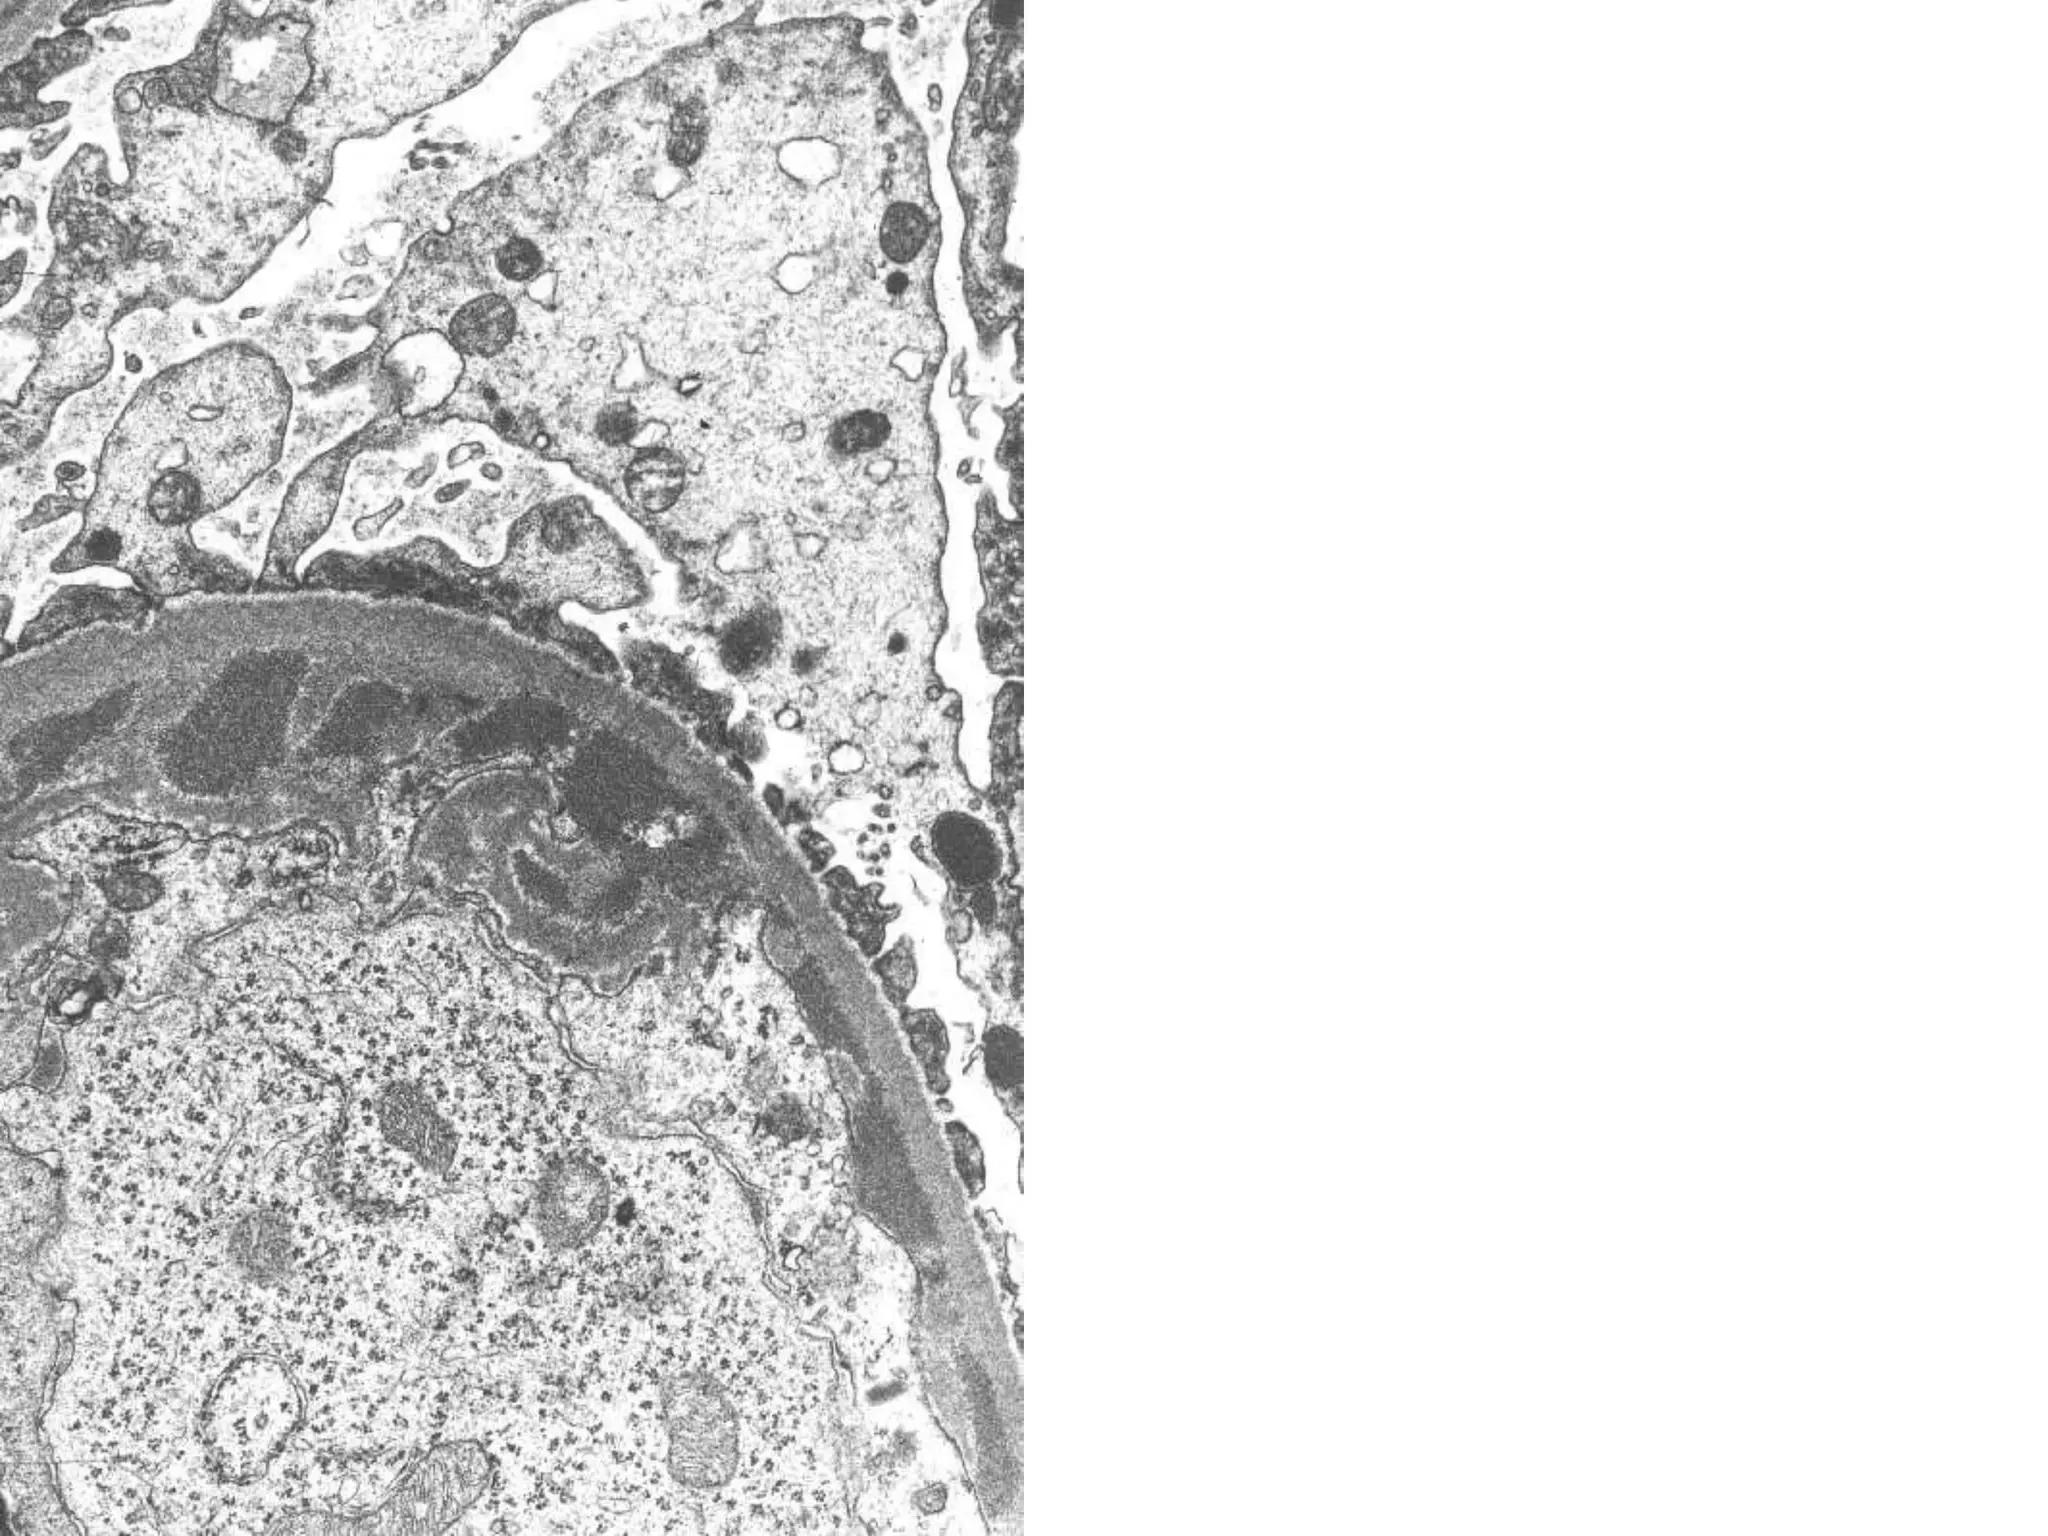

Mesangial electron dense deposits and increased mesangial matrix

and cellularity in IgA nephropathy

Pathogenesis • Deposition ofimmune complexes is the key • Mesangial and endothelial deposits have access to the vascular space. Leads to activation of complement, causing influx of leukocytes • Subepithelial deposits do not attract inflammatory cells

Mesangial electron densedeposits and increased mesangial matrix and cellularity in IgA nephropathy